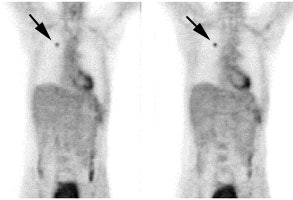

Lung cancer 1 cm lesion: The images below were from a patient with a 1 cm sized right upper lobe lung cancer. Note the excellent conspicuity of the lesion on FDG PET imaging. The exam was acquired using an ECAT EXACT PET scanner (CTI) with 5 min/bed emission and 2 min/bed segmented transmission. OS-EM iterative reconstruction was used for exam reconstruction. Case courtesy of Mallinckrodt Institute of Radiology/ Barnes Hospital, St. Louis and CTI PET Systems, Inc. |